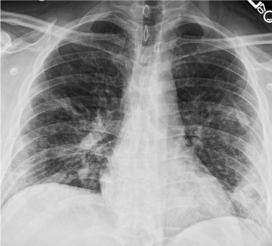

Стандартная РГ имеет низкую чувствительность в выявлении начальных изменений в первые дни заболевания и не может применяться для ранней диагностики. Информативность РГ повышается с увеличением длительности течения пневмонии. Рентгенография с использованием передвижных (палатных) аппаратов является основным методом лучевой диагностики патологии ОГК в отделениях реанимации и интенсивной терапии (ОРИТ). Применение передвижного (палатного) аппарата оправдано и для проведения обычных РГ исследований в рентгеновском кабинете. В стационарных условиях относительным преимуществом РГ в сравнении с КТ являются большая пропускная способность. Метод позволяет уверенно выявлять тяжелые формы пневмоний и отек легких различной природы, которые требуют госпитализации, в том числе направления в ОРИТ.

КТ имеет высокую чувствительность в выявлении изменений в легких, характерных для COVID-19. Применение КТ целесообразно для первичной оценки состояния ОГК у пациентов с тяжелыми прогрессирующими формами заболевания, а также для дифференциальной диагностики выявленных изменений и оценки динамики процесса. КТ позволяет выявить характерные изменения в легких у пациентов с COVID-19 еще до появления положительных лабораторных тестов на инфекцию с помощью МАНК. В то же время, КТ выявляет изменения легких у значительного числа пациентов с бессимптомной и легкой формами заболевания, которым не требуется госпитализация. Результаты КТ в этих случаях не влияют на тактику лечения и прогноз заболевания при наличии лабораторного подтверждения COVID-19. Поэтому массовое применение КТ для скрининга асимптомных и легких форм болезни не рекомендуется.

5. Рекомендовано проведение лучевого исследования пациентам при среднетяжелом, тяжелом и крайне тяжелом течении ОРИ с целью медицинской сортировки, оценки характера изменений в грудной полости и определения прогноза заболевания:

- выполнение КТ легких без внутривенного контрастирования в стационарных условиях или в амбулаторных - при показаниях к госпитализации;

- выполнение РГ легких в двух проекциях, если проведение КТ в данной медицинской организации/клинической ситуации невозможно.